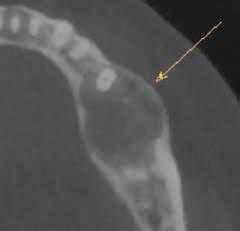

The use of a digital workflow to treat patients with APE has been proposed in situations with restorative treatments, as well as when no restorative treatment is anticipated.38,39 In this method, a CBCT scan is acquired to analyze the level of the alveolar bone crest in relation to the CEJ. An intraoral scan is acquired to aid in fabricating a surgical guide. Digital Imaging and Communications in Medicine files obtained from the CBCT are converted to Standard Tessellation Language format and then superimposed with Standard Tessellation Language files acquired from the intraoral scan. The level of the CEJ is then marked (Figure 5) to guide the gingivectomy incision line, followed by a second line 3 mm apical to the CEJ line to guide the bone resection.

TessellationLanguageformatandthensuperim posedwithStandardTessellationLanguage fi les acquiredfromtheintraoralscan.TheleveloftheCEJisthenmarked(Figure5 )toguidethe gingivectomyincisionline,followedbyasecondline3mmapicaltotheCEJlinetoguidethe boneresection.

Thevirtualdesignofthesurgicalguideisperformedaccordingly.Dataaretransferredtoa3D printer,andtheguideisprinted.Afterplacingtheguideinthepatient ’smouth,aninternal bevelincisionismadefollowingtheupperborderofthewindowoftheguide(Figure6 ).The

Figure 5. After superimposition of the cone-beam computed tomographic scan and intraoral scan, the cementoenamel junction and future bone level are marked. Reproduced from Alhumaidan A, Alqahtani A, al-Qarni F. 3D-printed surgical guide for crown lengthening based on cone beam computed tomography measurements: a clinical report with 6 months follow up. Appl. Sci. 2020;10(16):5697, CC-BY 4.0. https://doi. org/10.3390/app10165697.39

Figures 5-7 are reprinted with approval from the authors.

The virtual design of the surgical guide is performed accordingly. Data are transferred to a 3D printer, and the guide is printed. After placing the guide in the patient’s mouth, an internal bevel incision is made following the upper border of the window of the guide (Figure 6). The guide is then removed, and a second sulcular incision is made. The secondary flap is removed while visualizing the new crown lengths. A full-thickness mucoperiosteal flap is elevated and the surgical guide is then placed again to determine the extent of osteoectomy needed (Figure 7). An osteoectomy is then performed, followed by osteoplasty to finalize buccal bone thickness. The guide is then positioned for a final check before sutures are placed, and hemostasis is ensured.

This technique provides guides for both gingival and bone resection, facilitating the surgical procedure and providing predictable outcomes. Using a precise outline of the anatomic CEJ location can compensate for the variability among patients and reduce the chance of

under- or overcontouring hard and soft tissues.